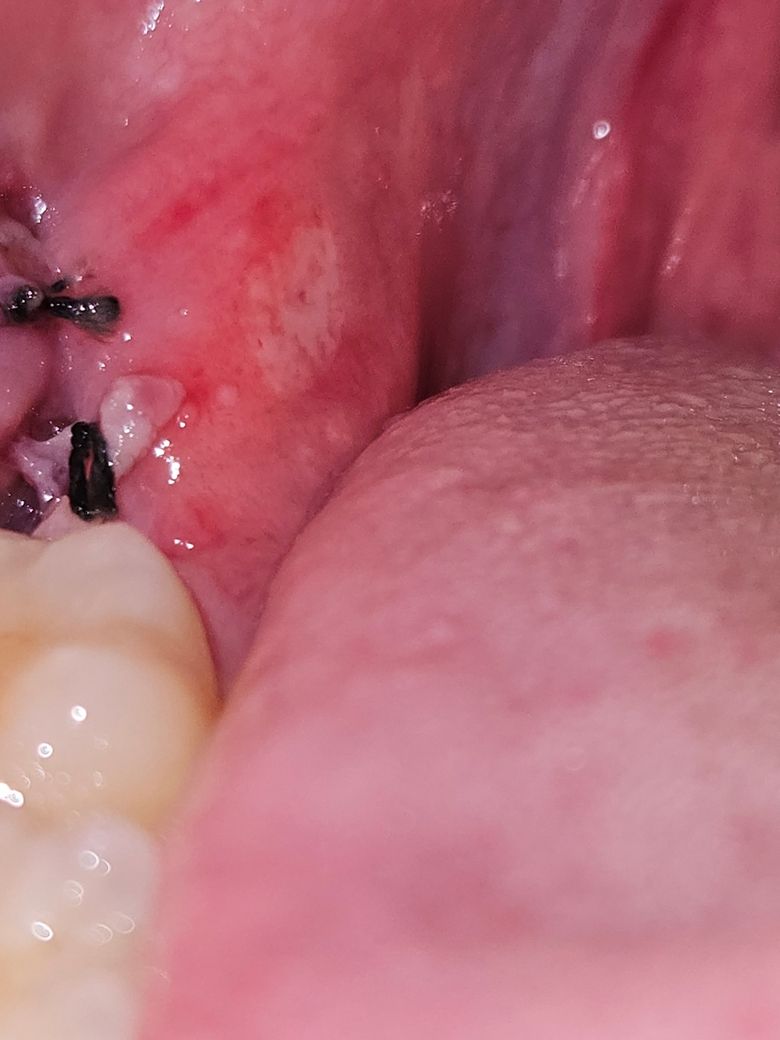

사랑니 발치 후 잇몸에 하얀 병변은 염증인가요?

사랑니 발치 후 5일째 입니다. 처음 2일차까지는 별로 통증이 없었는데, 3일차부터 사랑니 발치한 쪽의 볼에 구내염이 생기더니 5일차에는 잇몸에 하얀색 병변이 생겼습니다. 혹시 염증일까요? 그리고 구내염 치료 연고를 발라도 될까요?

• 1번 째 사진

발치를 하는 과정의 잇몸에 상처가 생길 수 있습니다. 이런 상처가 생긴 부위는 시간이 지나면서 하얄수 있는데 이런 하얀 부분은 잇몸이 아물게 되면서 점차 줄어들게 됩니다. 해당 부위를 자극하지 않는 것이 좋습니다.

아직 사랑니 발치를 한곳이 다 아물지 않아서 그러는거니 크게 걱정은 안하셔도 될것같습니다.